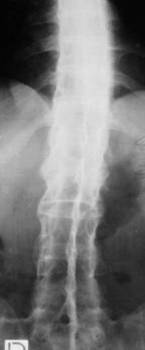

TUBERCULOZA COLOANEI VERTEBRALE (MORBUL LUI POTT)

Osteoporoza care este mai greu decelabila datorita suprapunerii tesutului pulmonar

Zone de osteoliza la nivelul platourilor vertebrale de dimensiuni uneori reduse, alteori interesând o mare parte din corpul vertebral

Pensarea spatiului articular

Vertebrele osteolizate se taseaza sub greutatea organismului predominant anterior, producându-se o cifoza în unghi ascutit.

Pe radiografia de fata, se observa, paravertebral bilateral, o opacitate de intensitatea partilor moi, cu aspect de fus - fusul pottic - data de abcesul rece care poate fuza uneori pâna la nivel inghinal

În evolutie, discurile vertebrale dispar, vertebrele, mai mult sau mai putin prabusite, se unesc între ele determinând un bloc vertebral. Numarul vertebrelor ce formeaza un bloc se poate determina numarând apofizele transverse (pe radiografia de fata) sau arcurile vertebrale si apofizele spinoase (pe radiografia de profil).